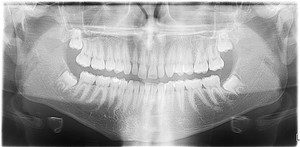

Panoramic System

A digital panoramic system is the newest addition to Brook Dental Associates technology. This digital machine allows us to have a full view of the mouth including the TMJ, wisdom teeth, and aides in implant diagnosis and placement.